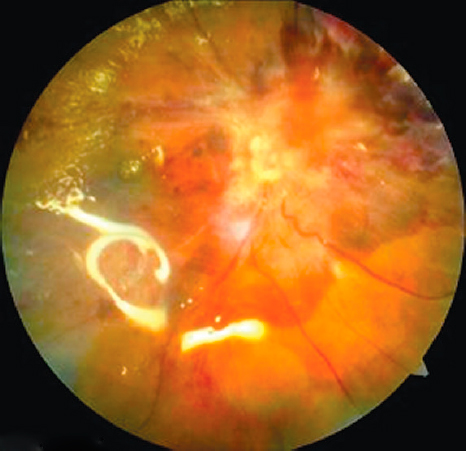

Во всех 55 глазах имел место сопутствующий гемофтальм (рис. 3). Его длительность варьировала от 2 нед. до 2 лет, в среднем — 6 мес. На 13 глазах он был тотальным, в 42 глазах — в виде взвеси эритроцитов в витреальной полости, преретинальных и витреальных геморрагий.

Рис. 3. Пациент В, 30 лет. Правый глаз. Гемофтальм, глиоз, тракционная отслойка сетчатки. Сахарный диабет 1-го типа на протяжении 20 лет. HbA1С 9%, нефропатия.